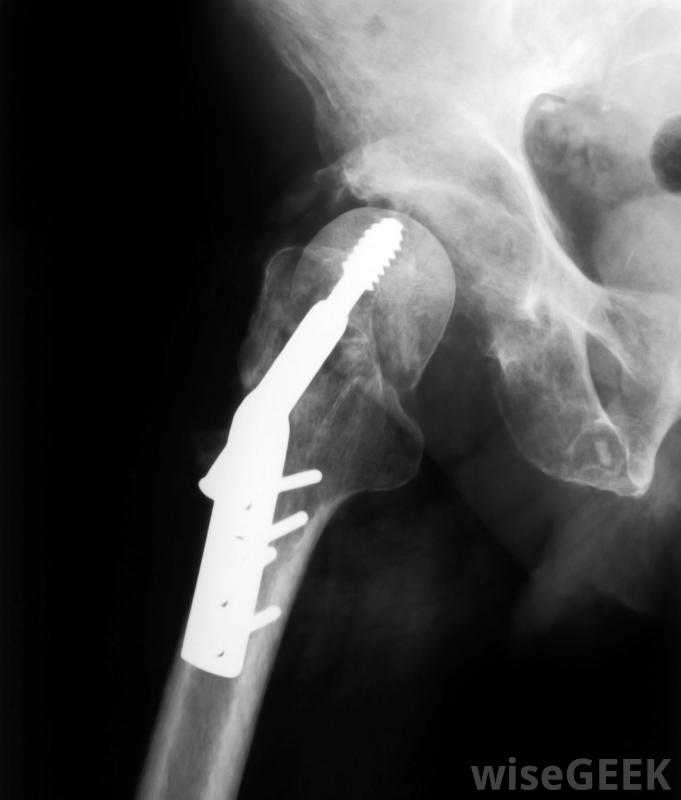

治疗上,抗重力跑步机可以让患者更快地移动,通过减轻患者受伤或新修复的关节、膝盖或臀部的重量,在康复过程中更早地建立肌肉张力。抗重力跑步机的应用还包括肌肉或腿部损伤,以及老年人的康复。

髋关节手术或髋关节手术后通常建议使用抗重力跑步机更换。